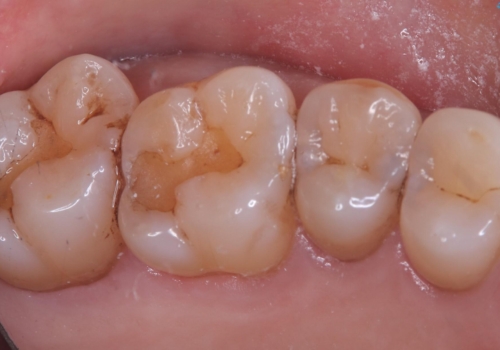

- 主訴:詰め物と歯の奥が側の境目に物がいつも溜まってしまう

保険適応のメタルインレーと歯質との間に不適合な箇所を認め、補綴物のやり替えでの治療となりました。インレーからクラウンへ補綴物の形態を変更し、素材は清掃性・適合性・審美性の点からセラミッククラウンでのやり替となりました。

レントゲン上にて、左上6番遠心にインレーと歯質の不適合を認めます。

健全歯質の残存量から、クラウンでのやり替えを提案しオールセラミッククラウン(スタンダード)でのやり替えとなりました。